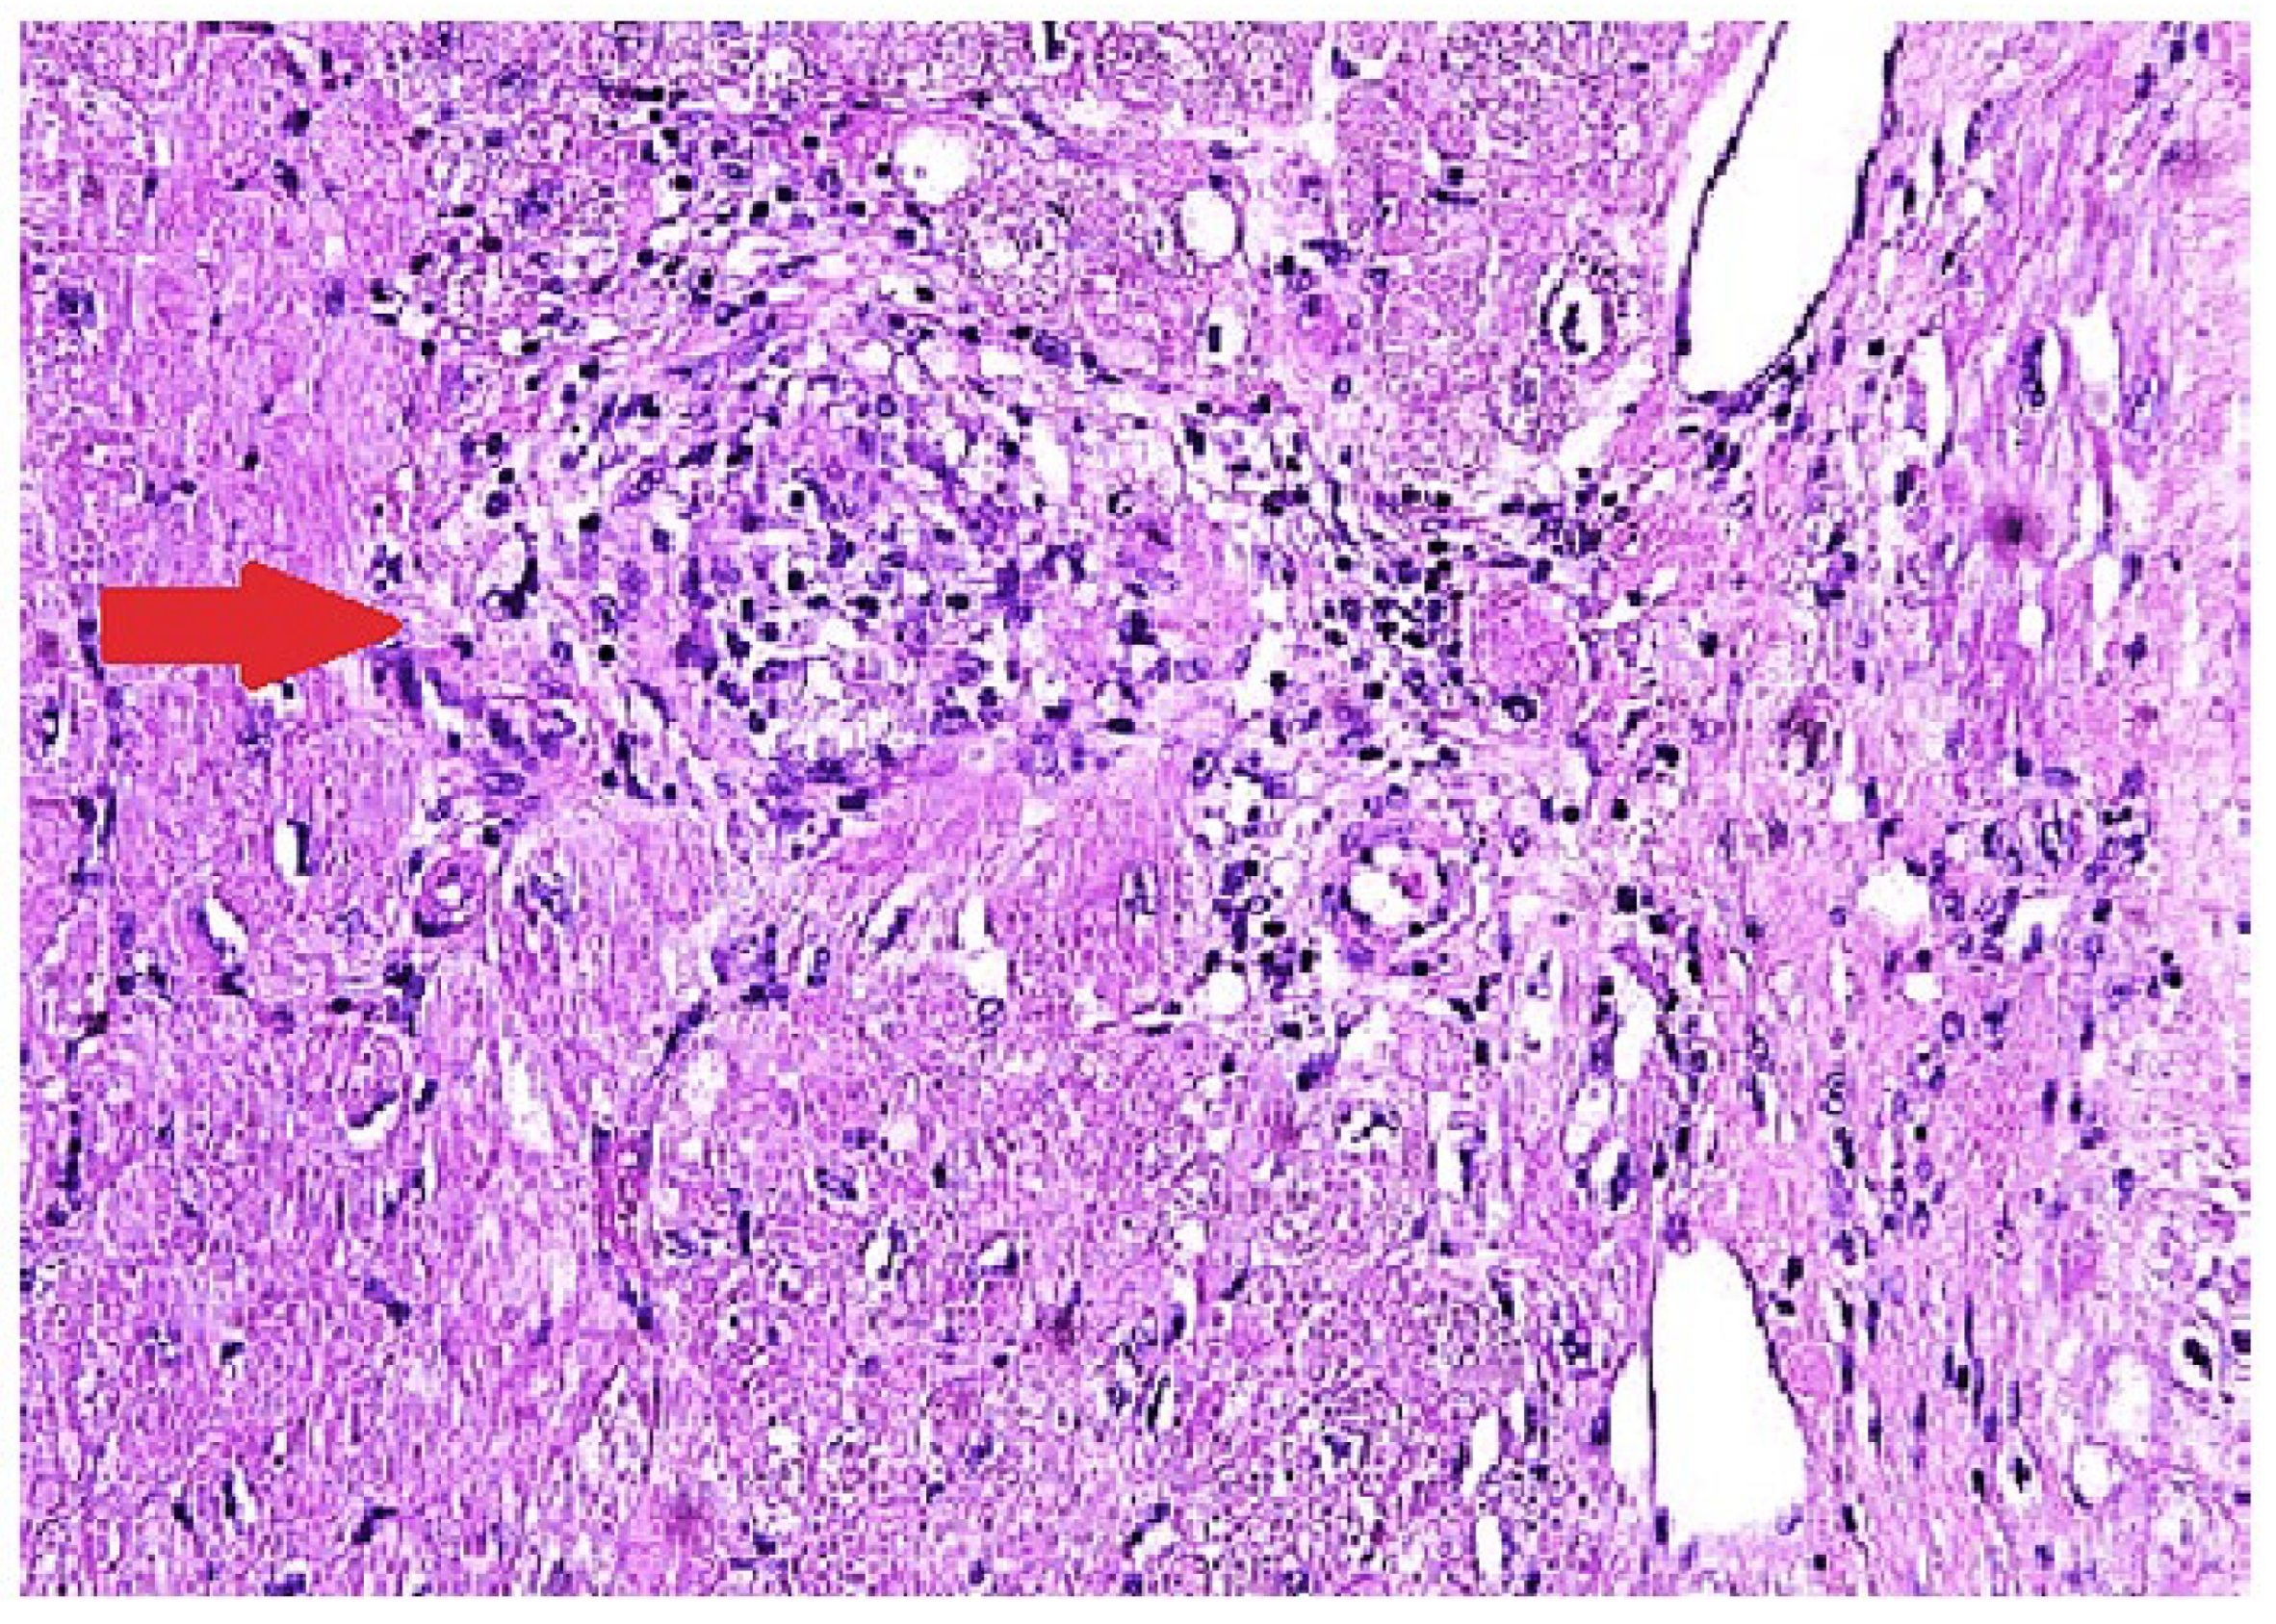

The most definitive way of diagnosing CS is through EMB showing histologic noncaseating granuloma with other causes excluded (Figure 2) [65]. The sensitivity of EMB for diagnosing CS was evaluated in a study that included 851 patients, and it demonstrated the sensitivity of EMB around 20% [66]. Several other studies showed similar results [67,68] The low sensitivity of EMB can be partially explained by the patchy involvement of the myocardium [69]. Higher sensitivity can be achieved with the aid of intracardiac voltage mapping or imaging guided EMB [70]. A study from Japan revealed higher positivity of EMB in patients with reduced left ventricular ejection fraction [71]. This could suggest that patients with severe cardiac injury and widespread disease activity are more likely to receive a histological diagnosis via EMB due to multifocal or diffuse changes.

Figure 2. Endomyocardial biopsy in a patient with cardiac sarcoidosis reveals a non-necrotizing granulomatous inflammation with patchy interstitial fibrosis on hematoxylin and eosin staining.